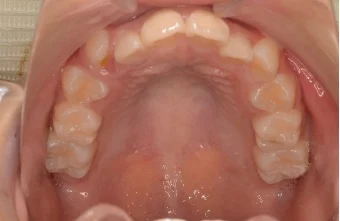

Case 1

| 主訴 | 凸凹を治したい |

|---|---|

| 年齢 | 10歳9ヶ月 |

| 性別 | 女性 |

| 期間 | 1年1ヶ月 |

| 種類 | 上下顎(拡大装置)+MBS(2×4) |

| 費用 | 基本装置¥200,000(税込¥220,000)+調整料¥5000(税込¥5,500)/回 |